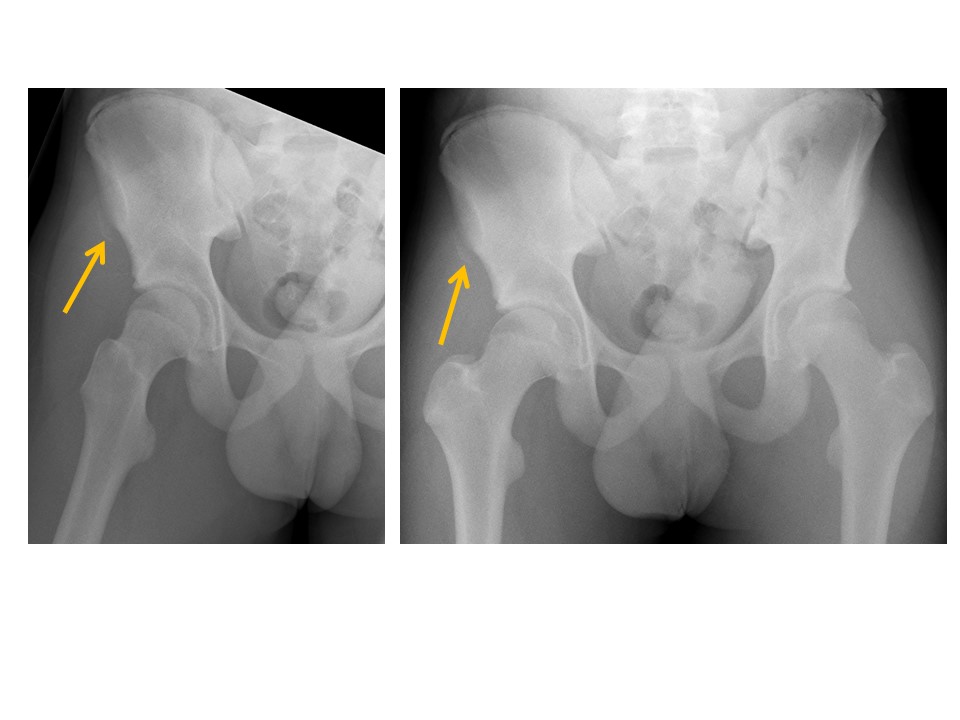

Anterior superior iliac spine avulsion fractures are present. [Yes/No]

Anterior inferior iliac spine avulsion fractures are present. [Yes/No]

There are avulsion fractures of the greater or lesser trochanters.

[Yes/No]